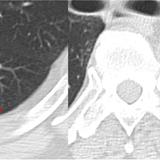

Rounded atelectasis case 1

Rounded atelectasis case 1 CT